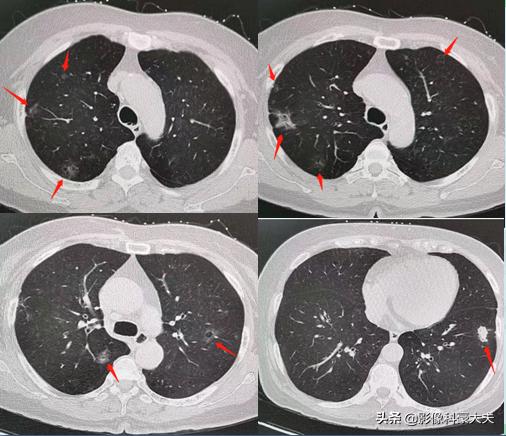

上图是我们今年遇到的另一例多原发肺癌,患者为54岁女性,有肺癌家族史。

有研究发现,多原发肺癌与遗传及后天获得性基因缺陷有关,比如杂合性缺失、p53、HER-2、K-ras过表达等。有肺癌家族史的肺癌病人更容易发生多原发肺癌。有一项基于瑞典人群的研究表明:有肺癌家族史的病人发生多原发肺癌的几率是无肺癌家族史病人的9倍。这方面还需要更多的大样本研究支持,如果能明确找出病因,也许会为此类高危人群提供预防肺癌的可行性办法。